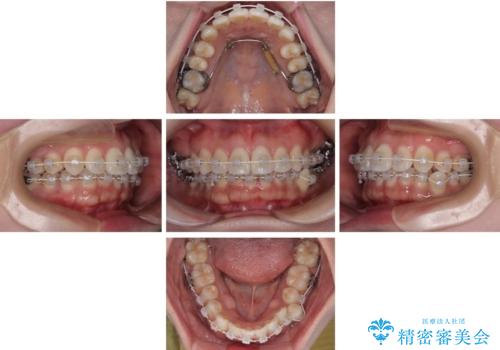

左下の小臼歯をきれいに歯列内へ並べるためには、まず十分なスペースの確保が必要でした。

そこで本症例では、上顎右側にアンカースクリュー(矯正用インプラント)を埋入し、そこからゴムかけ(顎間ゴム)を行うことで、下顎の正中を右方向へコントロール。

これにより、左下小臼歯がく並ぶためのスペースを確保することができました。

矯正中の見た目にも配慮し、プラスチックブラケット+コーティングワイヤーの目立ちにくい審美装置を採用しました。